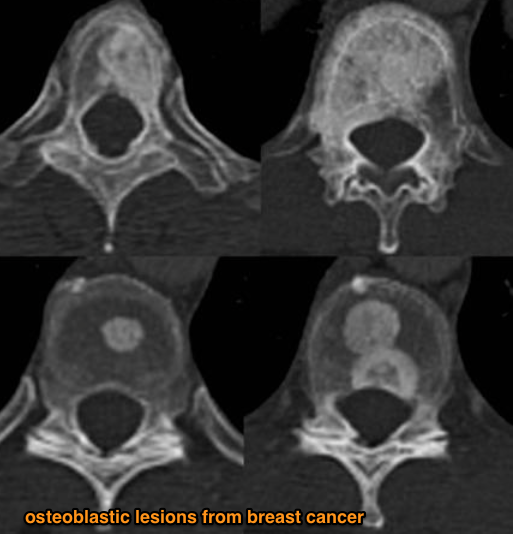

Describe metastatic cancer of bone?

What is the pathophysiology of bony mets?